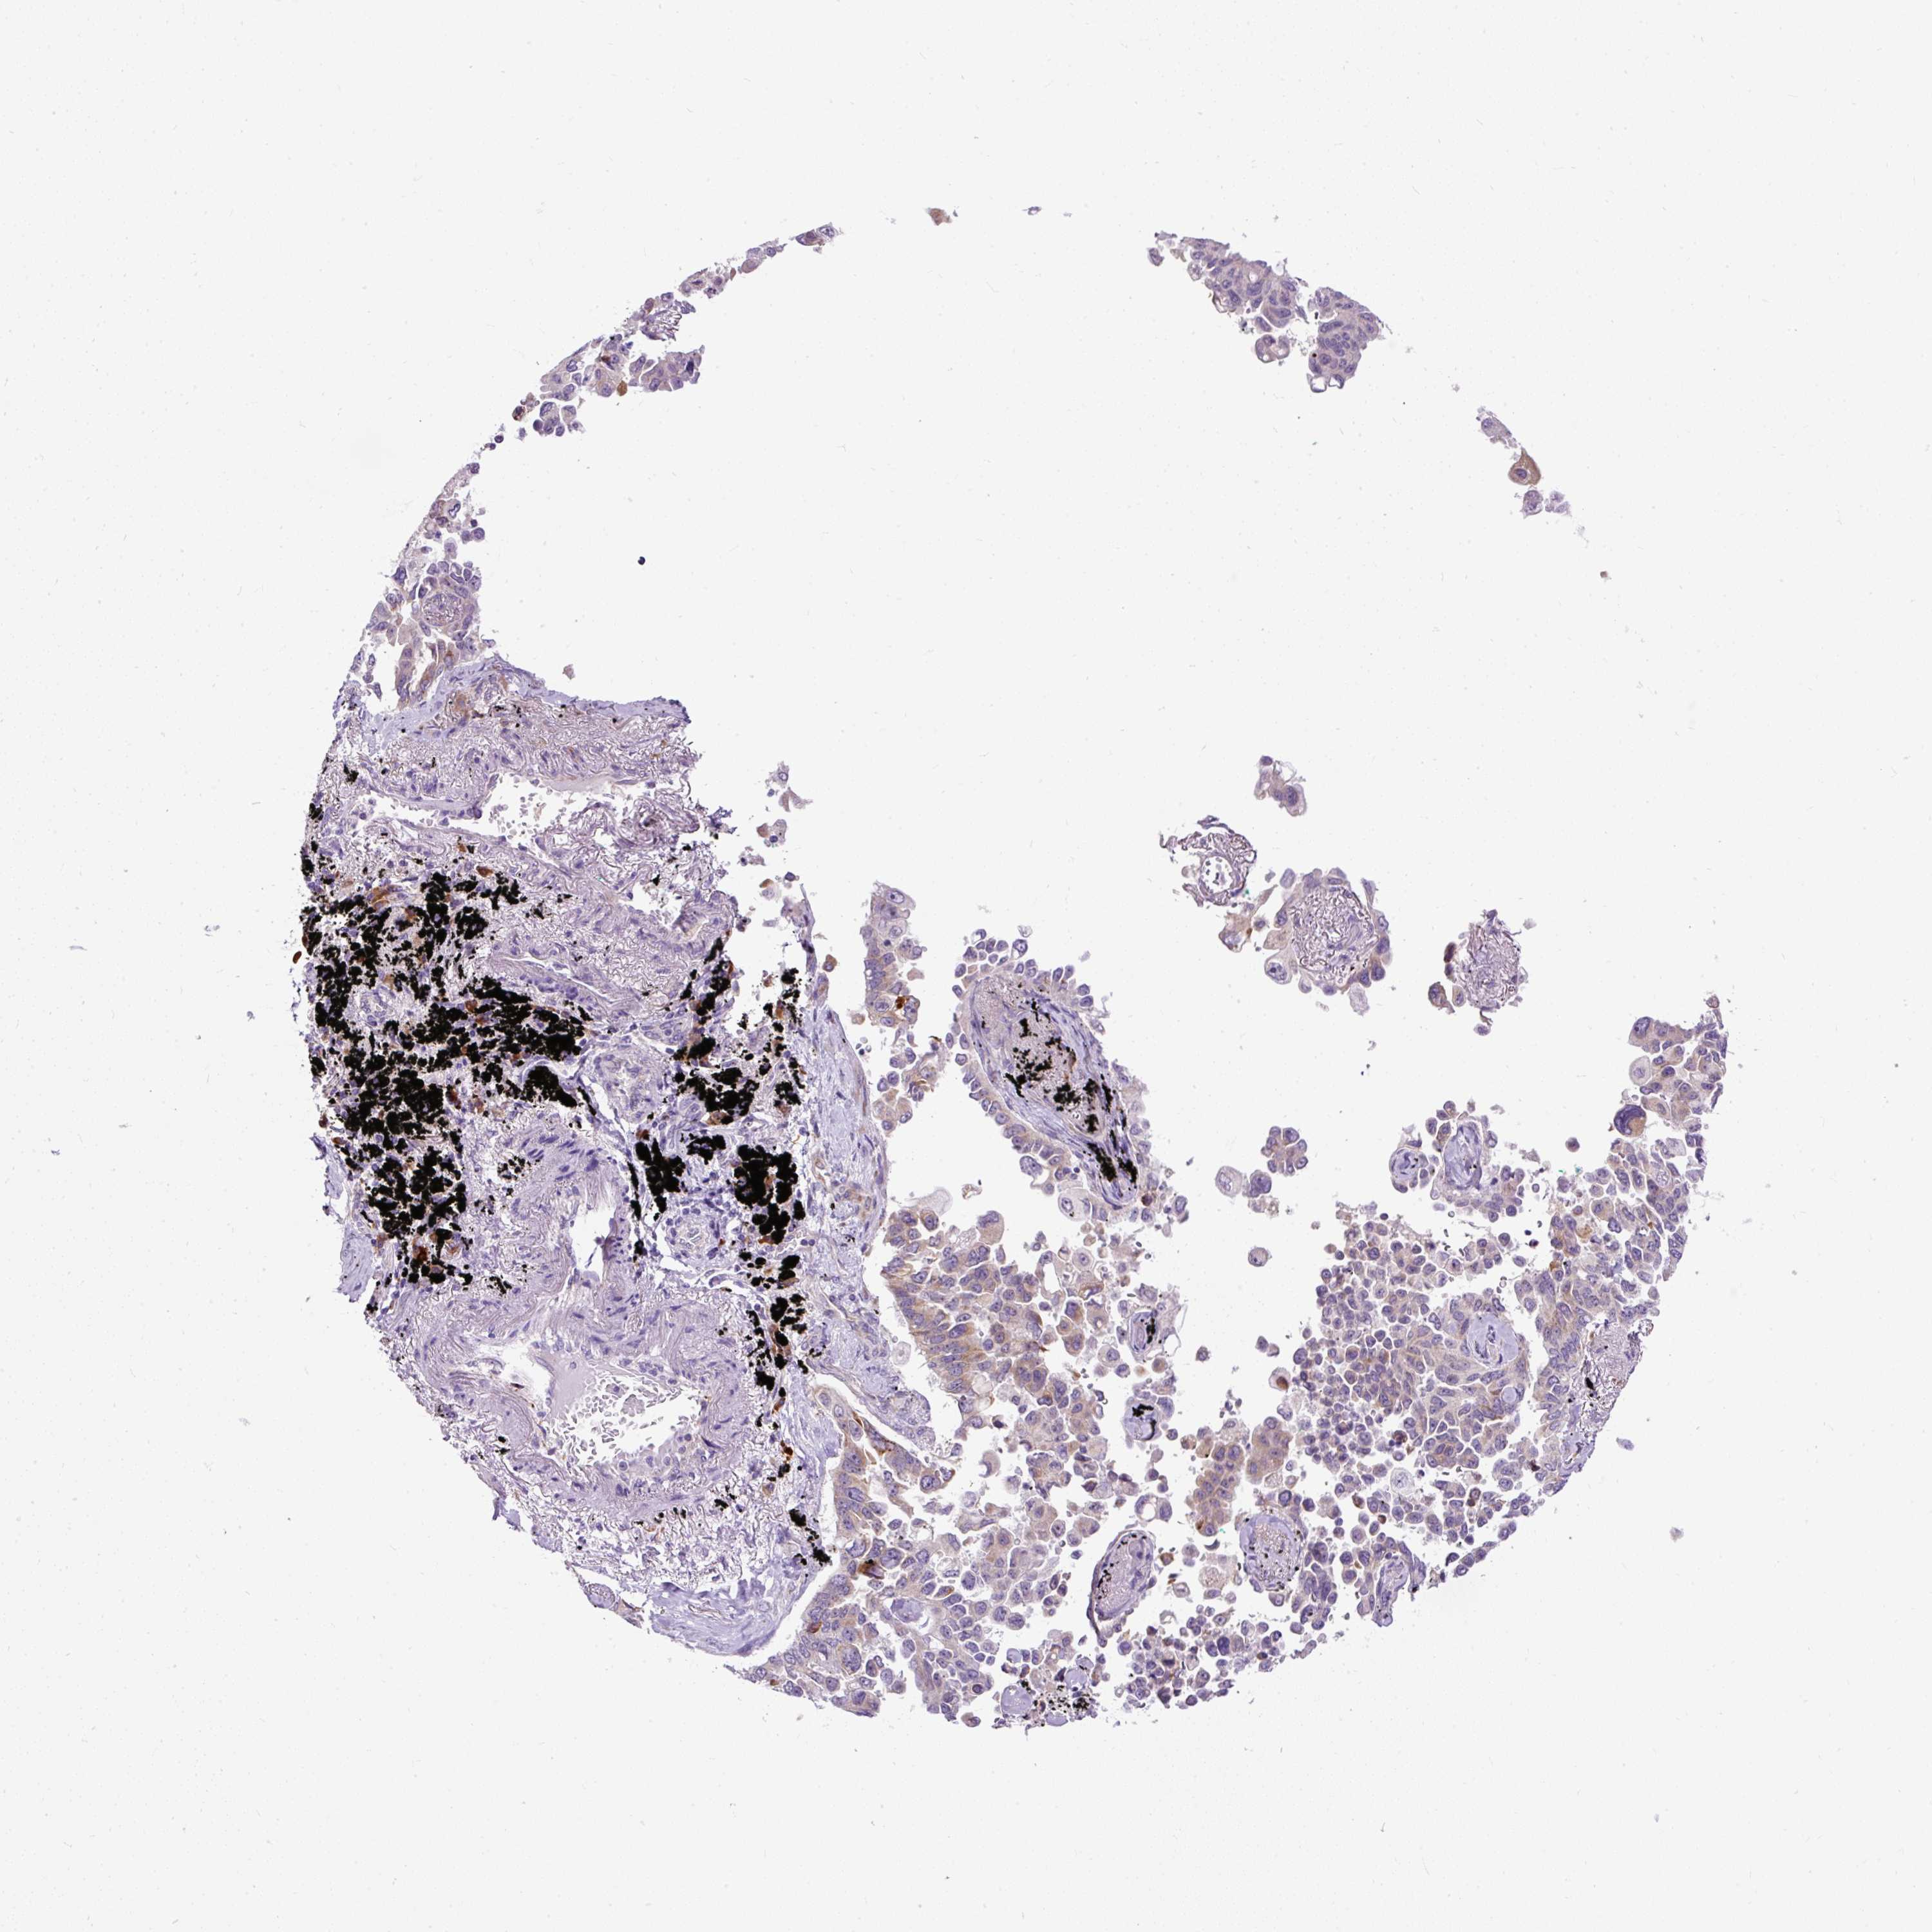

LUNG ADENOCARCINOMA (VALIDATION) - Interactive survival scatter ploti

The Survival Scatter plot shows the clinical status (i.e. dead or alive) for all individuals in the patient cohort, based on the same data that underlies the corresponding Kaplan-Meier plots. Patients that are alive at last time for follow-up are shown in blue and patients who have died during the study are shown in red.

The x-axis shows the expression levels (FPKM) of the investigated gene in the tumor tissue at the time of diagnosis. The y-axis shows the follow-up time after diagnosis (years). Both axes are complimented with kernel density curves demonstrating the data density over the axes. The top density plot shows the expression levels (FPKM) distribution among dead (red) and alive patients (blue). The right density plot shows the data density of the survived years of dead patients with high and low expression levels respectively, stratified using the cutoff indicated by the vertical dashed line through the Survival Scatter plot. This cutoff is automatically defined based on the FPKM cutoff that minimizes the p-score. The cutoff can be changed by dragging the vertical line or by entering a cutoff value in the square labeled "Current cut-off".

Under the Survival Scatter plot the p-score landscape (black curve; left axis) is shown together with dead median separation (red curve; right axis). Dead median separation is the difference in median mRNA expression between patients who have died with high and low expression, respectively. It is calculated as follows: median FPKM expression of dead patients with high expression - median FPKM expression of dead patients with low expression. This is intended to aid the user in visually exploring custom cutoffs and the associated p-scores and dead median separation.

Individual patient data is displayed and can be filtered by clicking on one or more of the category buttons on the top of the page. Categories describing expression level and patient information include: high, low, alive, dead, female, male and tumor stages. The scale of the x-axis can be toggled between linear and log-scale by clicking on the "x log" button. Mouse-over function shows TCGA ID, patient information and mRNA expression (FPKM) for each patient.

& Survival analysisi

Kaplan-Meier plots summarize results from analysis of correlation between mRNA expression level and patient survival. Patients were divided based on level of expression into one of the two groups "low" (under cut off) or "high" (over cut off). X-axis shows time for survival (years) and y-axis shows the probability of survival, where 1.0 corresponds to 100 percent.

FMC1 is not prognostic in Lung Adenocarcinoma (validation)

Best expression cut offi

Based on the FPKM value of each gene, patients were classified into two groups and association between prognosis (survival) and gene expression (FPKM) was examined. The best expression cut-off refers the FPKM value that yields maximal difference with regard to survival between the two groups at the lowest log-rank P-value. Best expression cut-off was selected based on survival analysis .

When clicking on this number, the vertical dashed line indicating cut-off, the interactive survival plot, and the Kaplan-Meier curve will be adjusted to show results based on the best expression cut-off.

: 4.36

Median expressioni

Median expression refers to the median FPKM value calculated based on the gene expression (FPKM) data from all patients in this dataset. When clicking on this number, the vertical dashed line indicating cut-off, the interactive survival plot, and the Kaplan-Meier curve will be adjusted to show results based on the median expression.

: N/A

Median follow up timei

Median follow up time refers to the median time (years) after diagnosis with this type of cancer, based on clinical data from all patients in this dataset.

P scorei

Log-rank P value for Kaplan-Meier plot showing results from analysis of correlation between mRNA expression level and patient survival.

N/A

5-year survival highi

5-year survival for patients with higher expression than the expression cutoff.

For melanoma and glioma, 3-year survival is shown.

5-year survival lowi

5-year survival for patients with lower expression than the expression cutoff.

TCGA RNA samplesi

RNA-seq data is reported as average FPKM (number Fragments Per Kilobase of exon per Million reads), generated by the The Cancer Genome Atlas (TCGA) .

Normal distribution across the dataset is visualized with box plots, shown as median and 25th and 75th percentiles. Points are displayed as outliers if they are above or below 1.5 times the interquartile range. FPKM values of the individual samples are presented next to the box plot.

Average pTPM 4.7

Number of samples 105